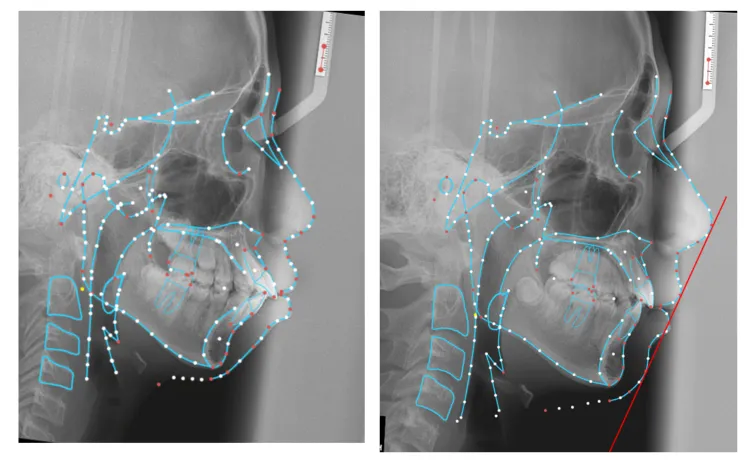

病例展示: